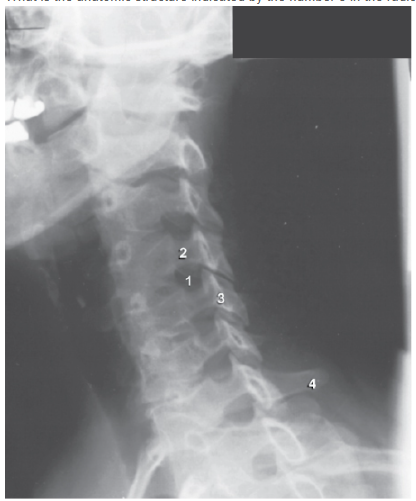

What is the anatomic structure indicated by number 1 in the radiograph shown below?

A - Superior articular process

An LPO projection of the lumbar spine is shown. The patient is positioned so that the lumbar spine forms a 45-degree angle with the IR. The zygapophyseal joints (those closest to the IR) are well demonstrated in this position. The typical “Scottie dog” image is depicted. The “ear” of the Scottie is the superior articular process (number 1), and the front foot is the inferior articular process (number 4). The Scottie’s eye is the pedicle, its body is the lamina (number 3), and its nose is the transverse process (number 2).

What is the anatomic structure indicated by number 4 in the radiograph below?

B - Inferior articular process

An LPO position of the lumbar spine is shown. The patient is positioned so that the lumbar spine forms a 45-degree angle with the IR. The zygapophyseal joints (those closest to the IR) are well demonstrated in this position. The typical “Scottie dog” image is depicted. The “ear” of the Scottie is the superior articular process (number 1), and the front foot is the inferior articular process (number 4). The Scottie’s eye is the pedicle (number 2), its body is the lamina (number 3), its nose is the transverse process (number 5), and its neck is the pars interarticularis (number 6).